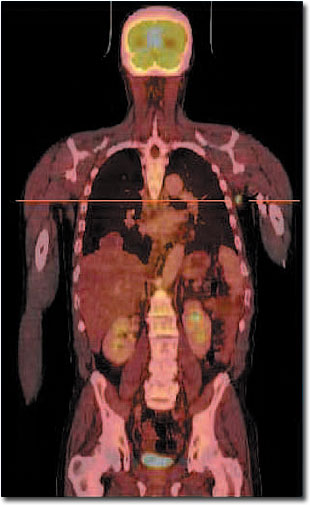

Ganzkörper-PET/CT, eingezeichnet ist die Schnittebene.

Bei einem Patienten mit Non-Hodgkin- Lymphom (Lymphknotenkrebs) wurde nach der Chemotherapie eine PET/CT durchgeführt. In der Achsel wird in der PET eine Lymphknotenmetastase sichtbar, die in der CT allein nicht zu erkennen ist. Anhand der PET/CT-Kombinationsaufnahme lässt sich die Metastase exakt lokalisieren. |